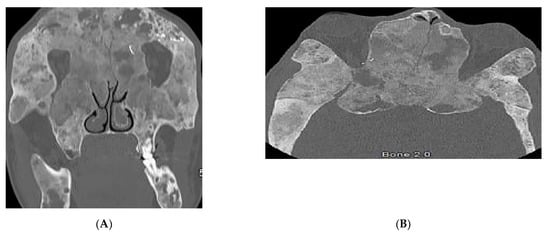

| Granulomatosis with polyangiitis (Wegner’s) | Palpable purpura Subcutaneous nodules Pyoderma-gangrenosum-like ulcerations Lung lesions and hemoptysis Glomerulonephritis Peripheral neuropathy, mononeuritis multiplex Chronic sinusitis and saddle nose deformity | Bilateral cavitary lung lesions with a ground-glass halo sign Mucosal thickening Nasal septal perforation Hyperostosis |

2.5. Granulomatosis with Polyangiitis